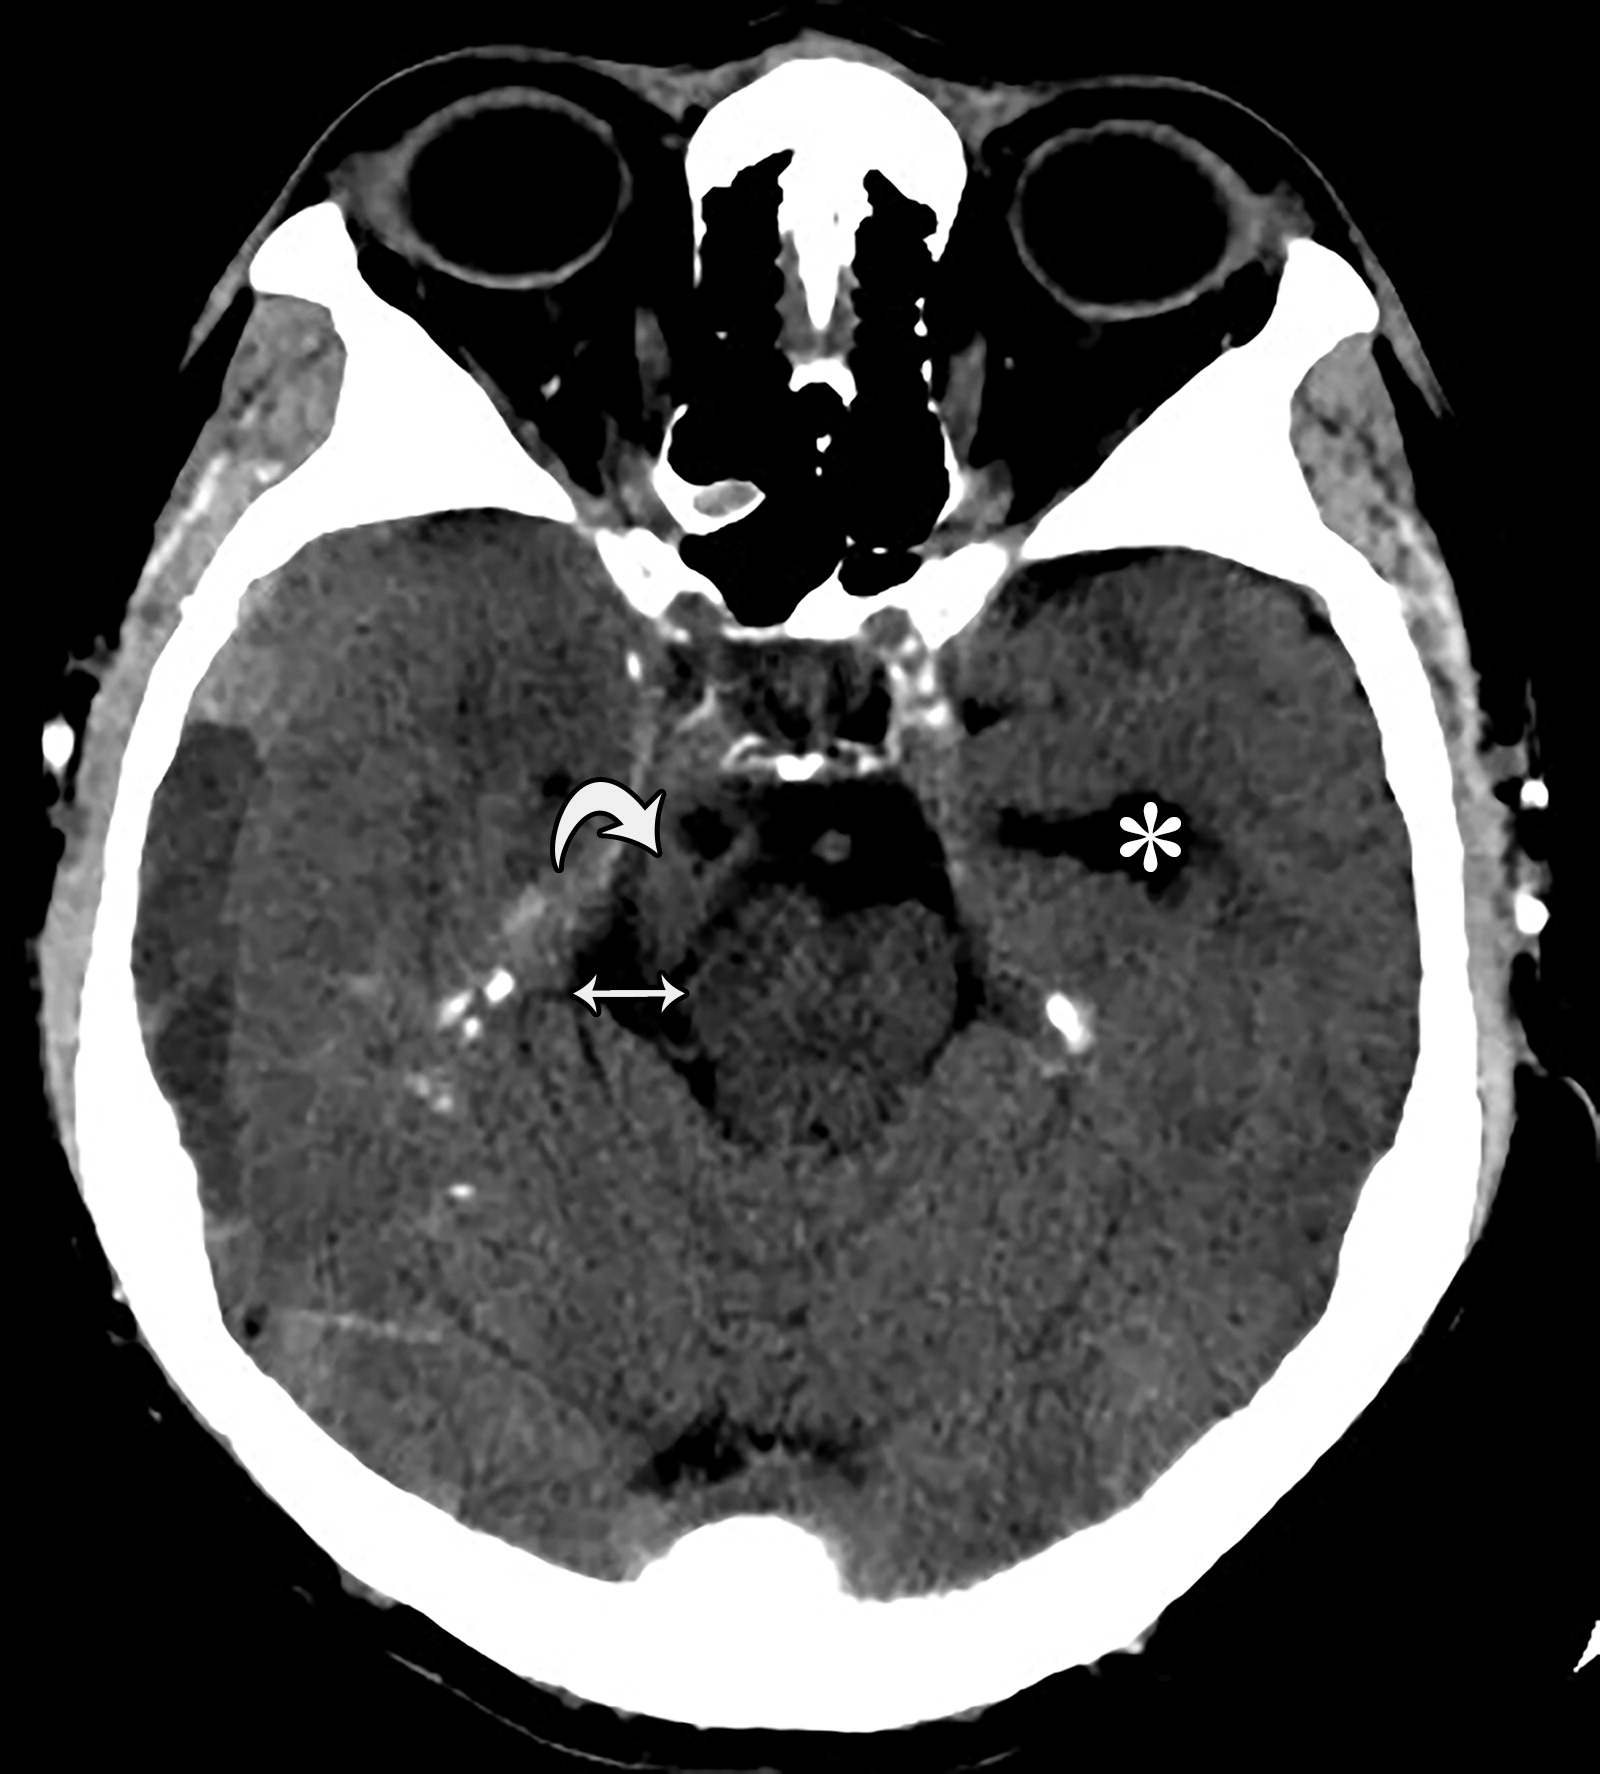

26岁男性,终末期肾病血液透析后硬膜下血肿,右侧瞳孔扩张,对光反射消失。钩回向下跨越小脑幕切迹(白色弯曲箭头),同侧的中脑周围池增宽(白色双箭头),对侧中脑周围池受压。注意对侧侧脑室的颞角增宽(*)。